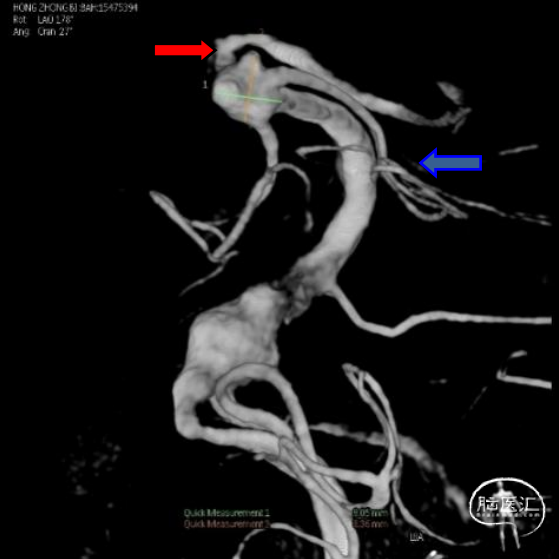

复查头颅CT提示广泛蛛网膜下腔出血,脑室扩张。基底动脉远端扩张请结合临床。急诊CTA提示:基底动脉两枚动脉瘤(图1)。

入院后立即行脑血管造影提示椎基底冗长扩张(基底动脉脑桥部分最宽处约5.2mm),伴有基底动脉多发动脉瘤,基底动脉尖动脉瘤(最大径约8mm)伴子囊和基底动脉下段动脉瘤(最大径约11mm)(图2)。